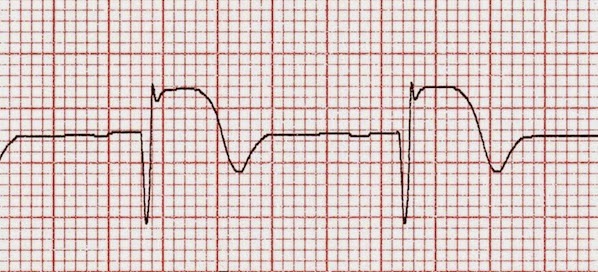

Control intensivo de la glucemia en diabéticos tipo 2 que reciben beta-bloqueadores

Un reanálisis del estudio ACCORD muestra que el tratamiento hipoglucemiante intensivo redujo los eventos cardiovasculares solamente en quienes recibían beta bloqueadores, pero aumentó la mortalidad en quienes no lo hacían. Se atribuye al efecto protector frente a las arritmias por hipoglucemia. Diabetes Care, octubre de 2016